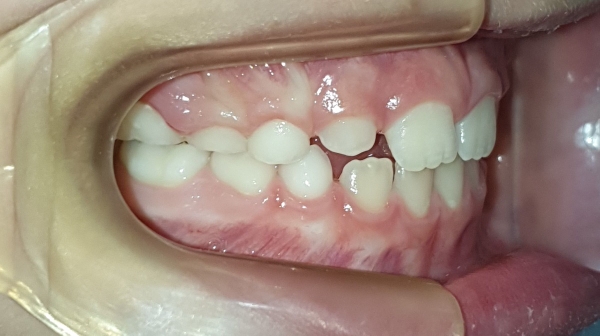

ANTES